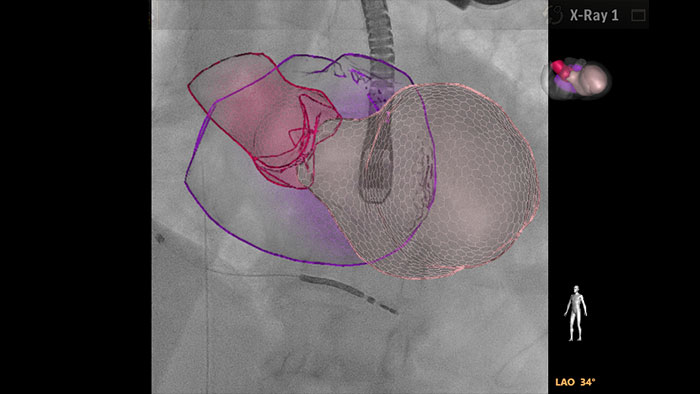

The HeartNavigator is a structural heart CT planning and live guidance solution using automatic heart model segmentation of anatomy to improve ease of use, speed and reproducibility of planning tasks, and adding the ability to overlay planned targets, landing zones and anatomical boundaries onto live fluoroscopy. In TAVR, HeartNavigator enables:

EchoNavigator reorients and combines ultrasound and X-ray information into a single augmented visualization for guidance and device-tissue relationship assessment. In TAVR EchoNavigator enables the following to eliminate iodine contrast in patients with severely compromised kidney function: